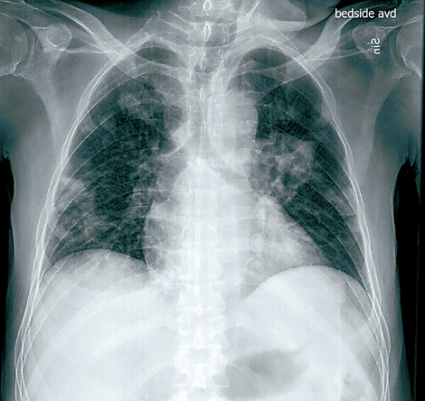

Patienten lades in på infektionskliniken, där han screenades och isolerades avseende multiresistenta bakterier. På misstanke om oral svampinfektion sattes nystatin in. Då patienten hade diarré togs fecesodling och prov för Clostridium difficile. Patienten fick syrgas på grimma. Lungröntgen visade bilaterala avrundade parenkymförändringar av oklar natur (Figur 1). Fynden ingav misstanke om malignitet alternativt tbc, varför man gick vidare med datortomografi av torax, buk och hjärna. DT-hjärna var utan anmärkning, men DT-torax visade en stor kavern i vänster ovanlob och bilateralt flera kaviterande förändringar med vätskenivåer samt en mindre mängd pleuravätska (Figur 2). På DT-buk sågs en ödematös kolonvägg. Clostridium difficile-toxin i feces var positivt, och behandling med metronidazol påbörjades. Svar på sedvanlig fecesodling var negativ. Den neurolog som konsulterades bedömde att patienten hade nedsatt kraft i benen men att han inte var totalt paraplegisk. MR-rygg beställdes.